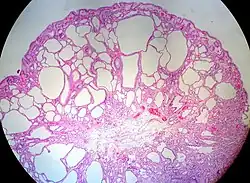

Micrograph of a Peutz–Jeghers colonic polyp – a type of hamartomatous polyp. H&E stain.